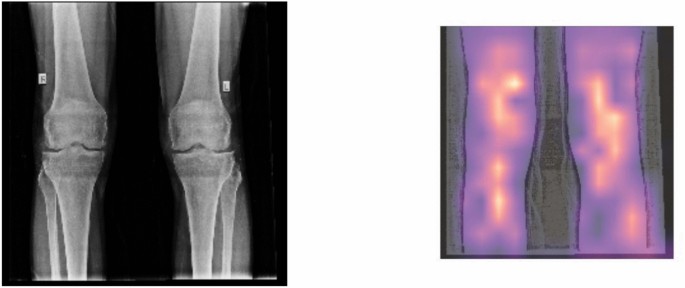

As it is clear from Table 3, the public dataset we accessed is not balanced. The class "osteopenic subjects" accounts for the vast majority of the data, whereas the other two classes barely make up a minute portion of the total. Therefore, it is to be expected that any classifier that is created around these data will contain some degree of bias. Figure 4 displays three examples of the dataset images.

We also went through the examination of the power of these two types of models, via another method. We utilised heatmap visualisations to evaluate their effectiveness in detecting illness locations in medical pictures. The main goal was to assess the precision and comprehensibility with which each model identifies problematic regions. The heatmaps obtained showed that the ViT s16 model outperformed the VGG16 model in reliably identifying the affected areas. The heatmaps generated by the ViT s16 model offer a higher level of accuracy and clarity in identifying specific regions of pathology. This highlights its potential as a more efficient tool for detecting diseases in medical imaging applications. The results indicate that the sophisticated structure of the ViT s16, which utilises self-attention processes, provides notable benefits in medical picture analysis compared to the conventional convolutional method of VGG16. Figures 12 and 13 manifest the result of the comparison for aforementioned two models.